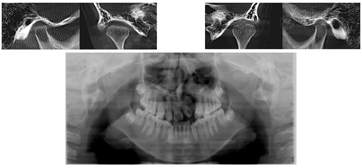

CBCT检查结果可见牙根形态、平行度良好,双侧颞下颌关节髁突及关节窝形态正常,间隙正常,见图10。